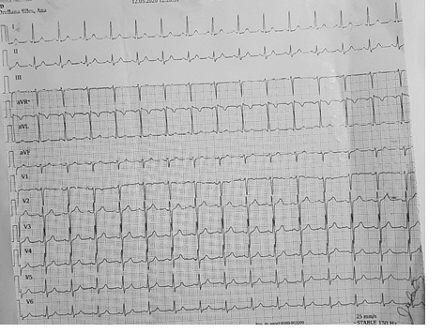

? Reporte de Electrocardiograma (12/05/2020): ritmo sinusal, FC de 80 lpm. Ver figura 2.